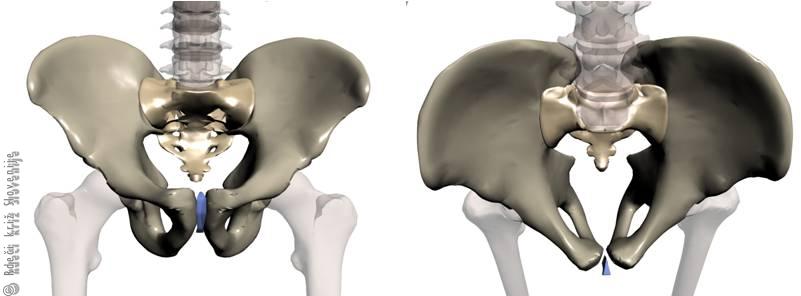

Slika 1

Skelet moške medenice.

Slika 2

A – Prerez ženske medenice.

B – Prerez moške medenice.